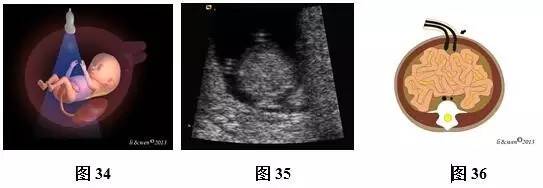

(三)11~13+6孕周胎儿腹部扫查方法及观察内容

超声扫查方法:声束通过胎儿上腹部的胃泡、肝脏横断扫查(图31),可获得上腹部横切面图(图32,33),然后声束平面向胎儿尾侧平移扫查,通过脐带腹壁插入口时(图34),可获得脐带腹壁插入口横切面(图35,36)。通过膀胱时(图37),可即获得膀胱水平横切面(图38,39)。

标准切面判断标准:腹部呈圆或椭圆形,脊柱为横切面,上腹部横切面可见正常胃泡位于左侧,肝脏位于右侧;脐带腹壁插入口横切面可见脐带腹壁入口位于前腹壁中央,与后腹壁脊柱回声连成一直线构成此平面的前后中轴线;膀胱水平横切面彩色多普勒可见膀胱位于盆腔内,呈无回声,在膀胱的两侧各有1根脐动脉,略向脐孔处旋转探头,可见脐血管在腹正中处进入脐带内。

主要观察的内容:(1)上腹部横切面:主要观察内容是胃泡及肝脏位置、大小。正常胃泡位于腹腔左侧,肝脏位于腹腔右侧。(2)脐带腹壁插入口横切面:腹壁完整性与连续性,脐带腹壁入口处位置是否正常、有无包或肠管外翻等。(3)膀胱水平横切面彩色多普勒:观察脐动脉数目,膀胱位置、大小及壁的厚度等。

注:ST为胃泡;LIVER为肝脏;SP为脊柱;IVC为下腔静脉;AO为腹主动脉;UA为脐动脉;L为左侧;R为右侧;

图31~39 11~13+6孕周胎儿腹部扫查方法、声像图及模式图。图31上腹部横切面图扫查模式图;图32、33上腹部横切面图声像图及模式图;图34脐带腹壁插入口横切面扫查模式图;图35、36脐带腹壁插入口横切面声像图及模式图(黑色箭头示脐带腹壁入口);图37膀胱水平横切面扫查模式图;图38、39膀胱水平横切面彩色多普勒。